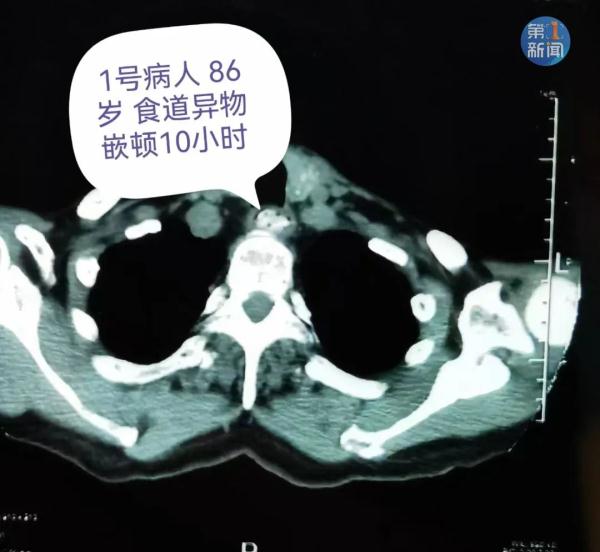

仅西安交大一附院消化内科

就接诊了9例枣核卡在食道里的病人

西安交通大学第一附属医院 消化内科 副主任医师 张娟:“6月3号接诊过程中,我们接到了8个因为枣核卡在消化道前来做异物取出的病人,有的病人枣核卡在食道里,有的进入了胃里但是没有办法进入肠道,也需要内镜下把枣核取出来。”

记者了解到

枣核卡入消化道的患者中成年人居多

医生接诊的这些患者中

有的枣核甚至卡在消化道里十多个小时